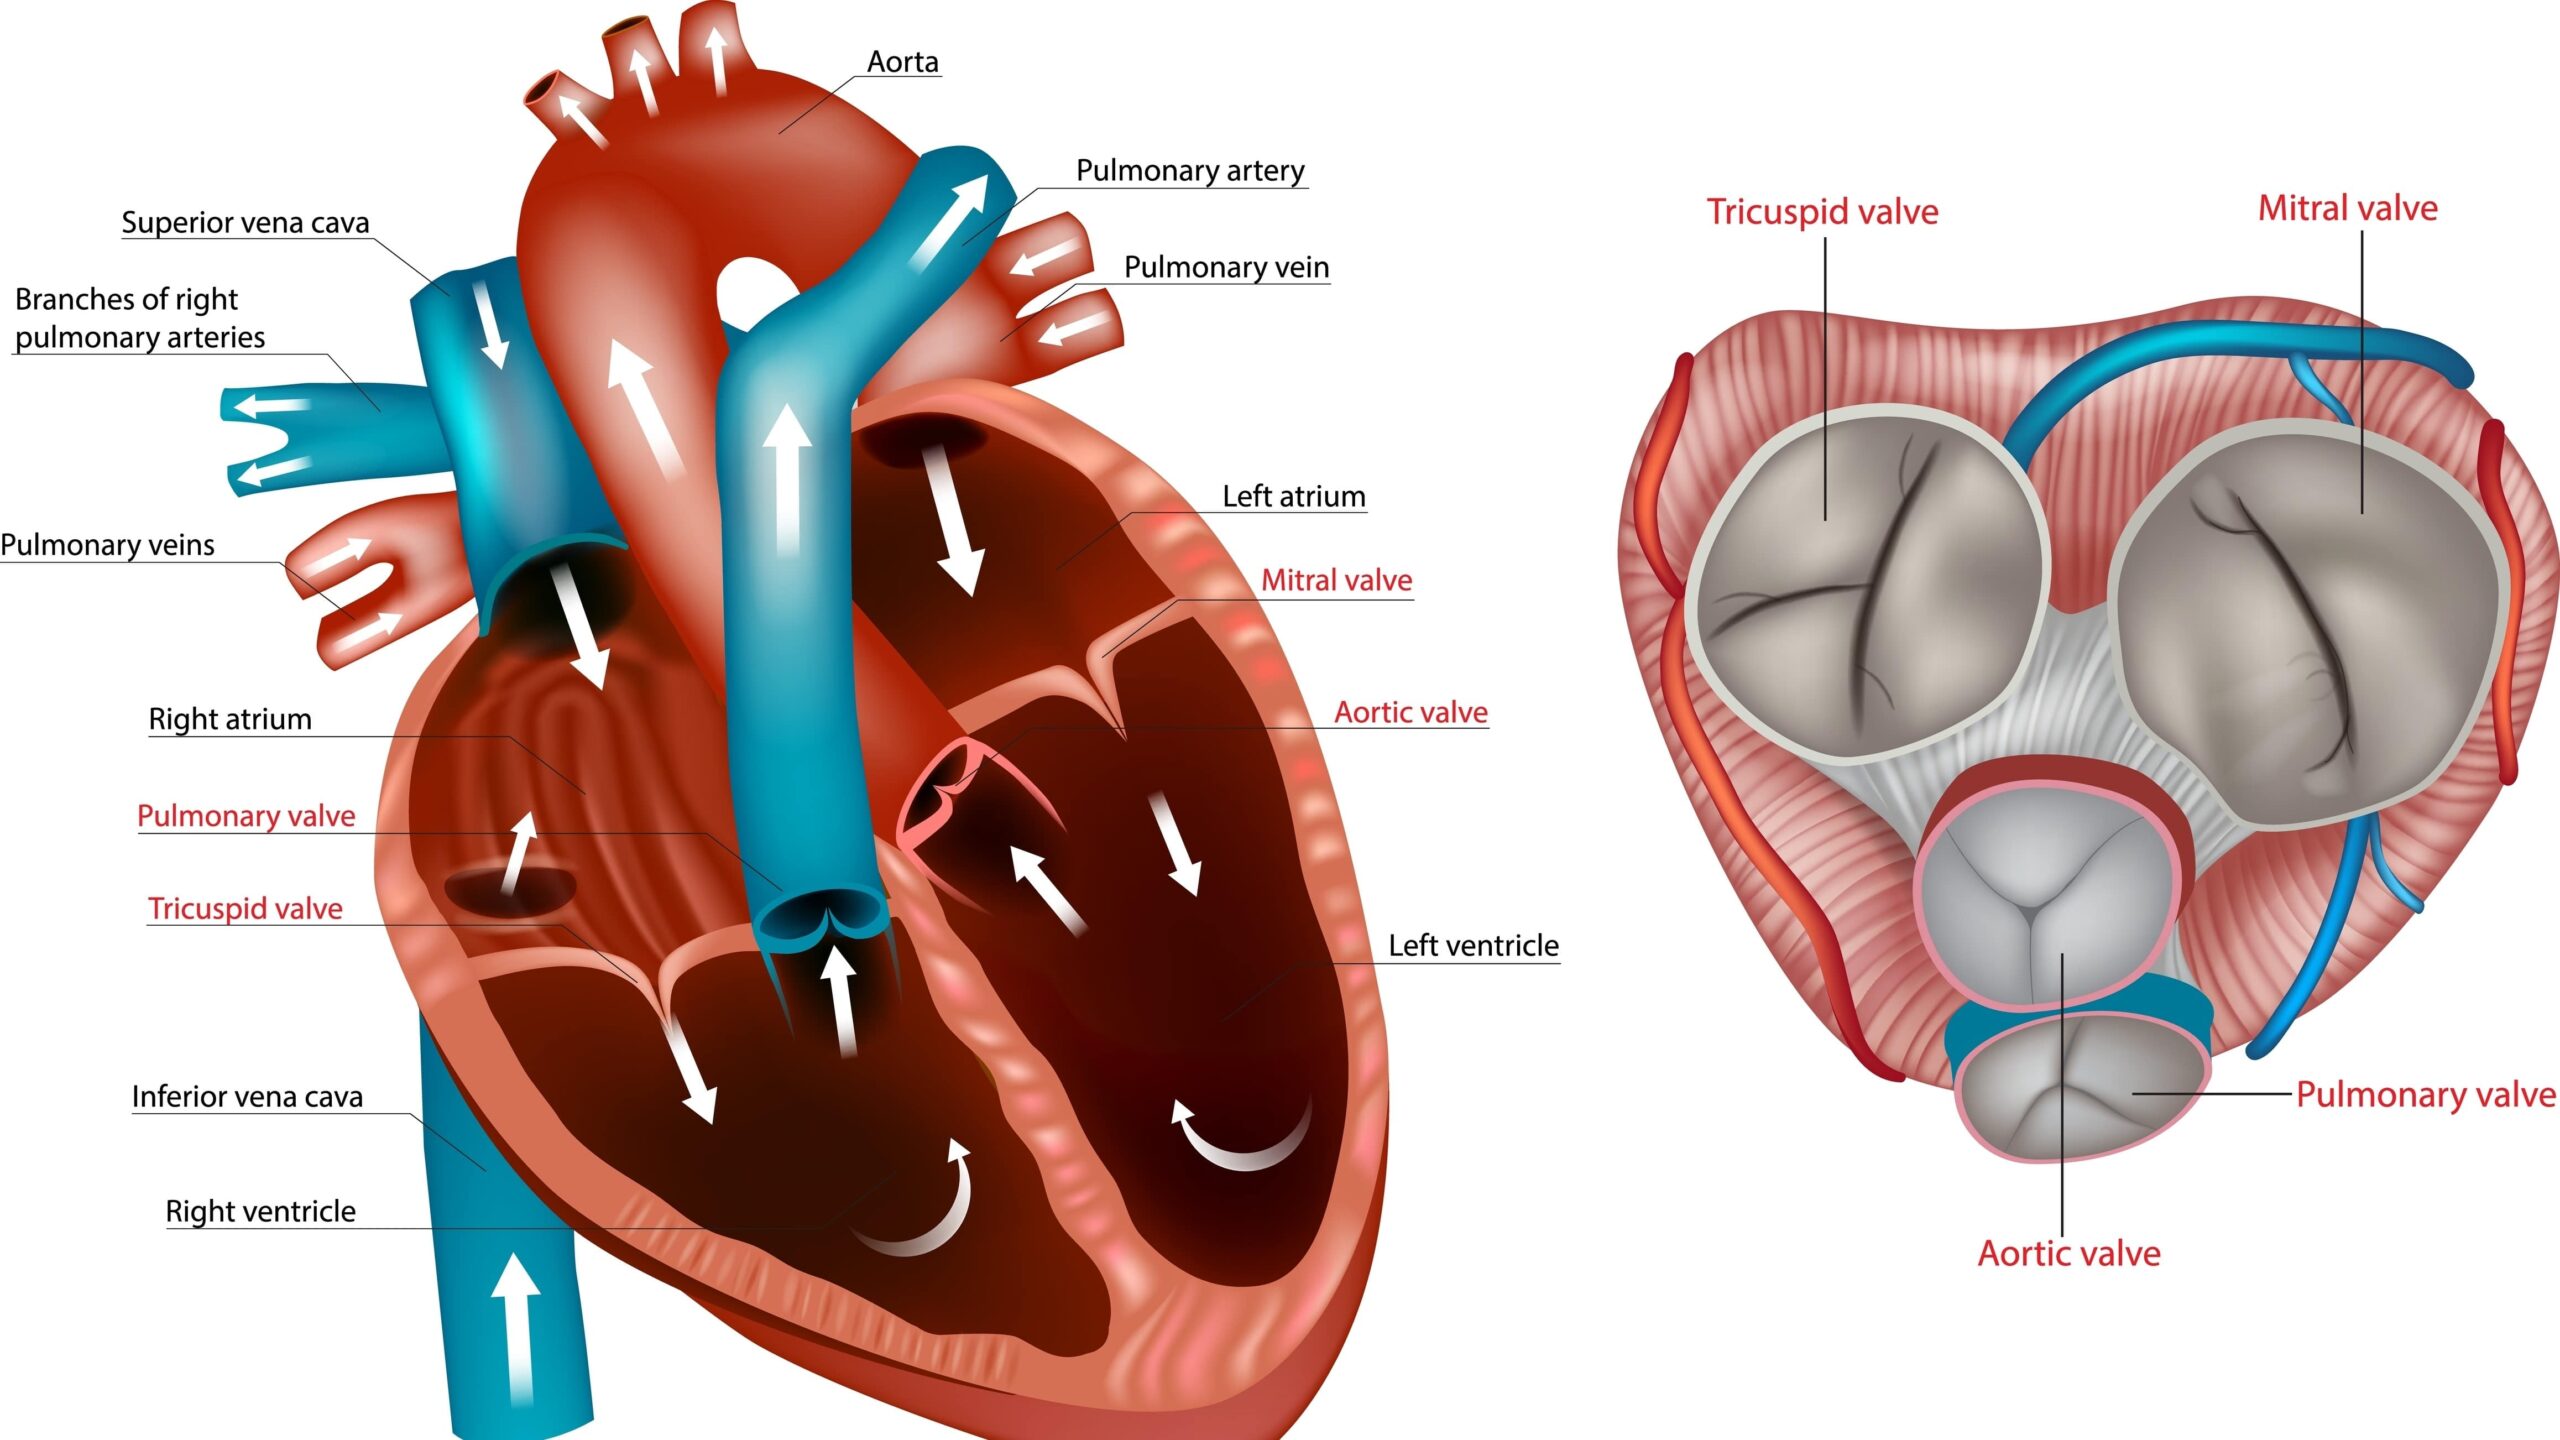

Heart disease is the most common cause of death worldwide, and in 2020, heart disease led to the death of nearly 700,000 ...Patrick DalyAtrial Fibrillation | April 7, 2023